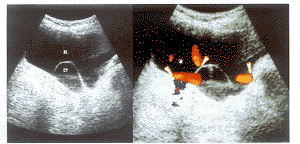

摘 要 目的:评估三维超声、彩色多普勒超声对输尿管囊肿的应用价值。方法:用三维、彩色多普勒血流观察了10例输尿管囊肿的立体形态及喷尿情况。结果:三维超声立体感强,形态逼真,定位准确。彩色多普勒显像示喷尿的尿流束由囊肿内向膀胱喷射时较为明显,表现为细而色艳的彩色流束,而由输尿管向囊肿内喷射时流束则呈粗而色暗。结论:三维超声和彩色多普勒超声能提高诊断输尿管囊肿的准确率,为临床提供更准确的诊疗信息。